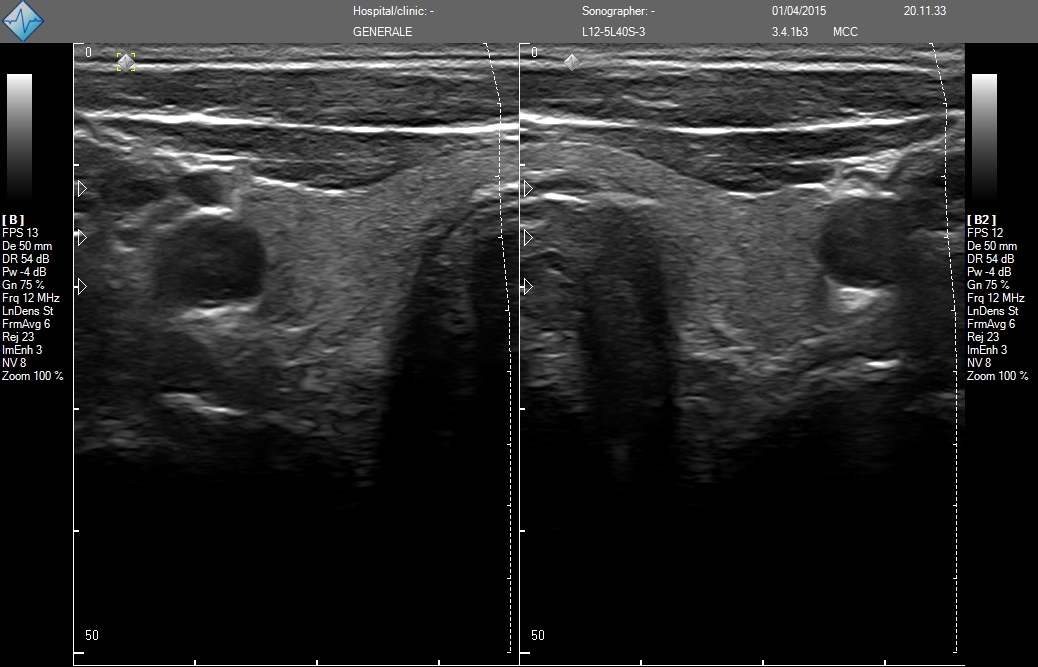

- MicrUs Pro-L40S (линейный, 5-12 МГц, 40 мм)

MicrUs Pro-L40N (линейный, 5-12 МГц, 40 мм, производительная версия)

MicrUs Pro-C60S (конвексній, 2-5 МГц, R60 мм)